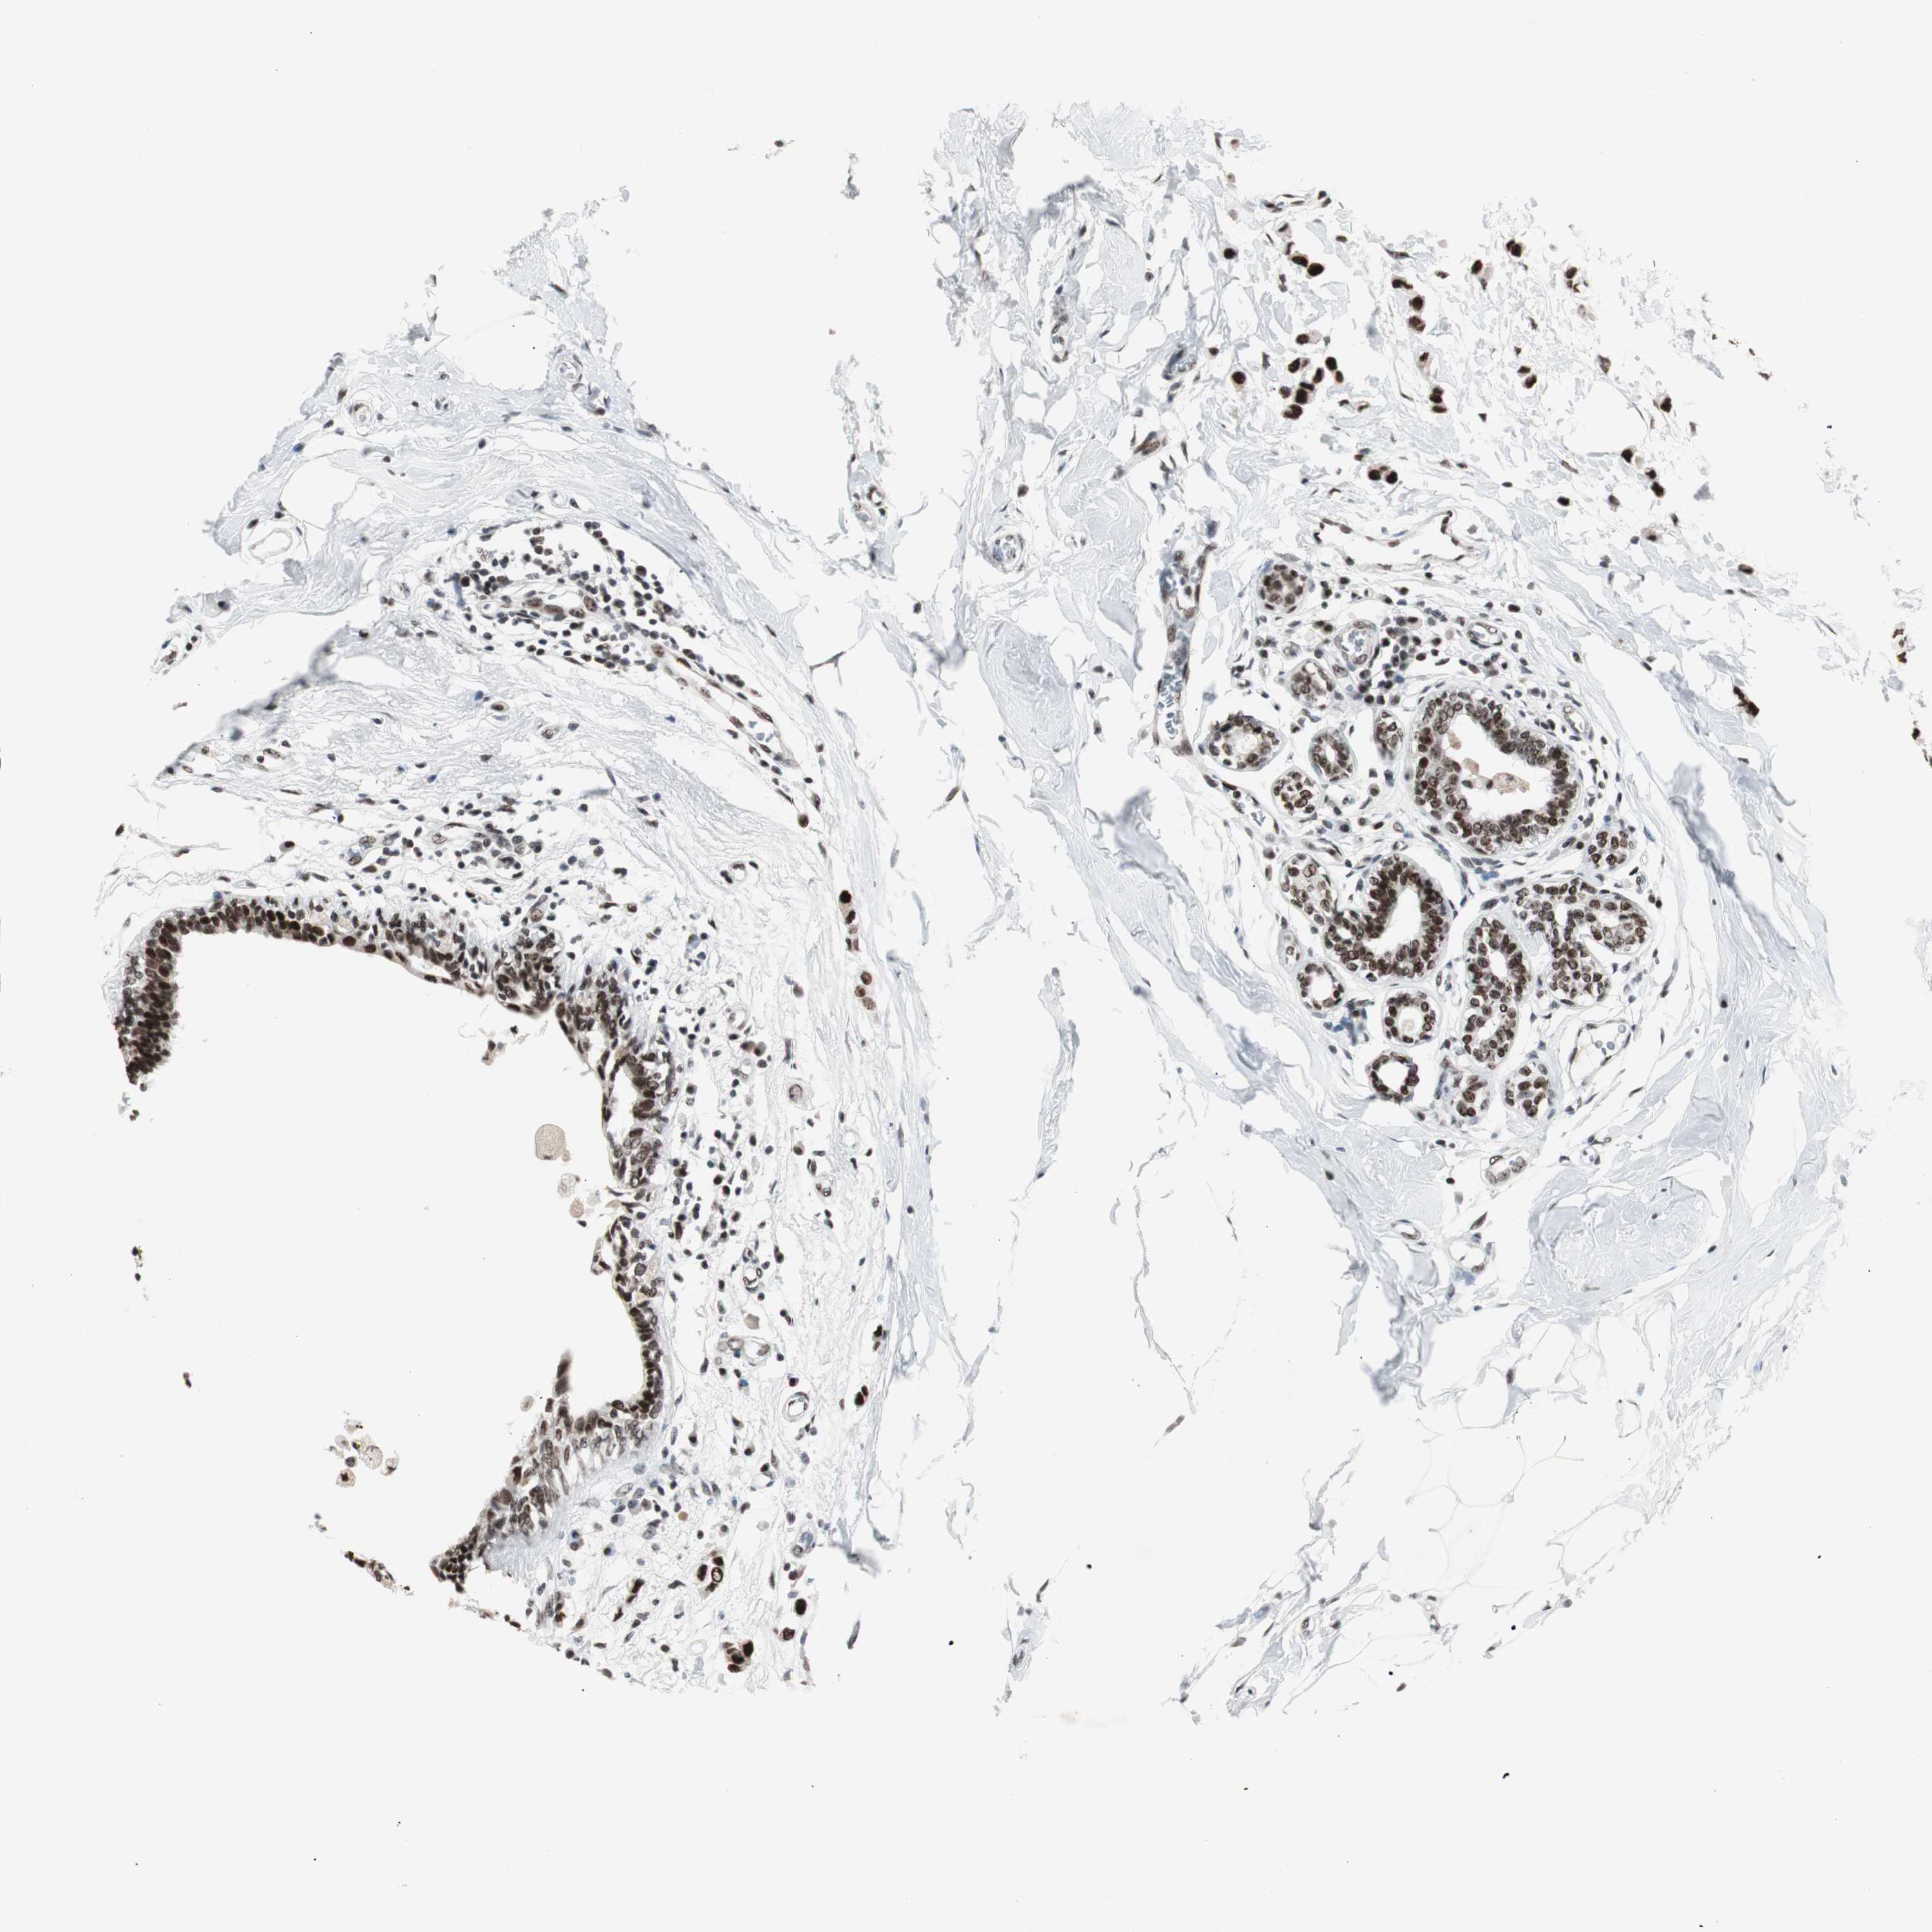

CANCER BREAST CANCER Show tissue menu

BRCA TCGA BRCA VALIDATION PROTEIN EXPRESSION

ANTIBODIES

AND

VALIDATION